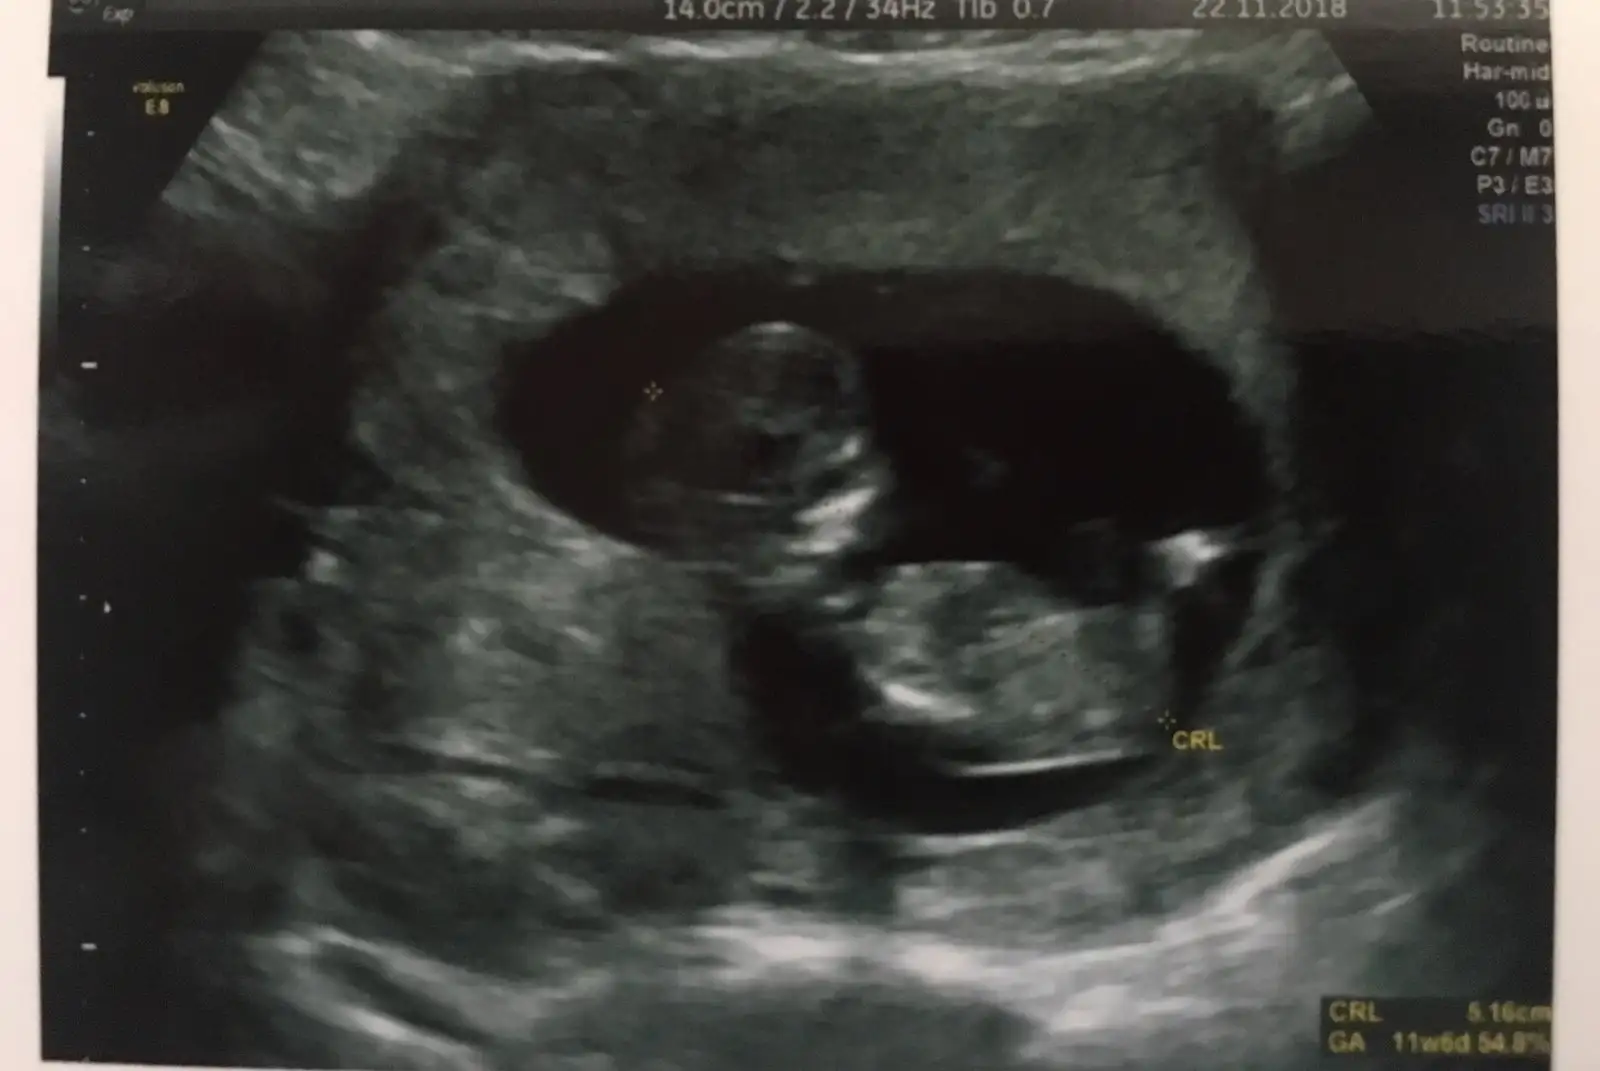

Büyük ihtimalle kız dedi canım ama kesin demedikçe tam emin olamıyor insan :)) Benimde ultrasonda 12+2 ydi burda. Ama sata göre 11+5

Böyle alttan goruntusunu hep gosterdı ordan da bakıyordu cınsıyet degılde dr bıseyler olcup dınlıyor ben cınsıyet anlamaya calısıyorum tabı ama doktor bana bacak arasından degıl baska bıyerden anlıyorz dedı

Banada bacak arasına bakıp anlıyoruz dedi demekki her doktorun stili farklı :)) Bende inceliyorum ama son kontrolde kıpır kıpırdı göremedim pek biryerlerini :)

Kendı doktorum degldı canım perinatolog baktı ıkılıye o oyle dedı 12+2 falandım galıba bu haftalarda oraya gore soylemem dedı.. bılmıyorum kı acaba nerden bilemedımmmm meraktayımmmmmmm bakalım kendı doktorum ne soyleyecek